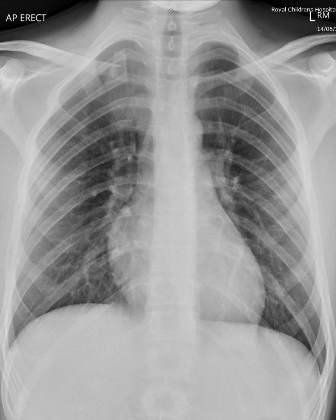

A 15-year-old boy was hit on his right shoulder, while playing football. Physical examination showed pain, swelling and deformity of the left SC area and of the medial fourth of the clavicle. Hollow area was felt next to the right sternoclavicular joint. Neurovascular examination was normal and there was no sign of dysphagia or dyspnea.

Fig. 1: X-ray chest showing both clavicles